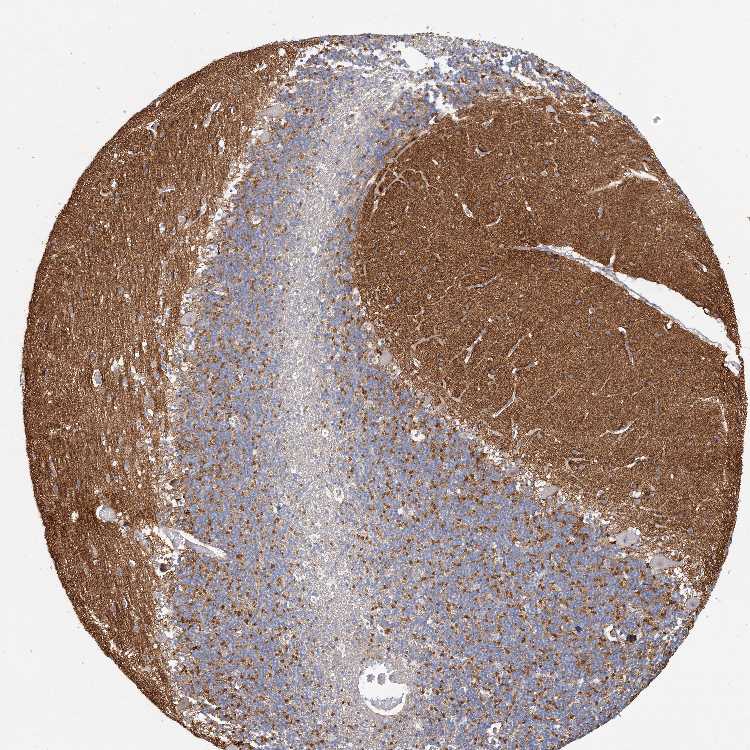

CEREBELLUM - Antibody stainingi

Antibody staining in the annotated cell types in the current human tissue is reported as not detected, low, medium, or high, based on conventional immunohistochemistry profiling in selected tissues. This score is based on the combination of the staining intensity and fraction of stained cells.

Each image is clickable and will lead to virtual microscopy that enables deeper exploration of all samples and also displays staining intensity scores, fraction scores and subcellular localization as well as patient and tissue information for each sample.

Antibody HPA035512Antibody HPA035513

Purkinje cells Not detectedNot detected

Cells in granular layer MediumNot detected

Cells in molecular layer Not detectedNot detected